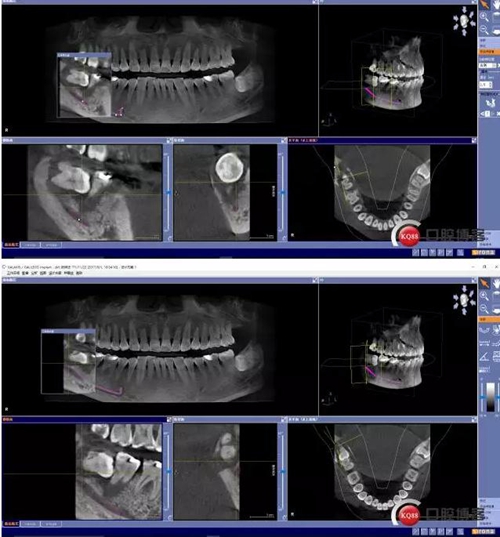

X線及CBCT檢查:47、48根尖周區(qū)大面積低密度影像,波及下牙槽神經(jīng)管,部分區(qū)域至神經(jīng)管以下。CBCT顯示神經(jīng)管走形于47根尖炎癥區(qū)下方(已侵犯)48炎癥區(qū)頰側(cè)(已侵犯)

術(shù)前CBCT分析

術(shù)后影像分析

對(duì)于曲面斷層片的分析,當(dāng)智齒埋伏牙的根尖與下牙槽神經(jīng)有重疊影像時(shí),常??刹捎糜^察重疊部分牙根的牙周膜和硬骨板是否連續(xù),下頜管是否比牙根密度高,下頜管是否變窄等,來辨別牙根與神經(jīng)管的位置關(guān)系。當(dāng)然曲面斷層片也很難避免其失真變形的自身局限性。拍攝CBCT能更為直觀預(yù)估其風(fēng)險(xiǎn)。但切記盲目的嘗試和挑戰(zhàn)。